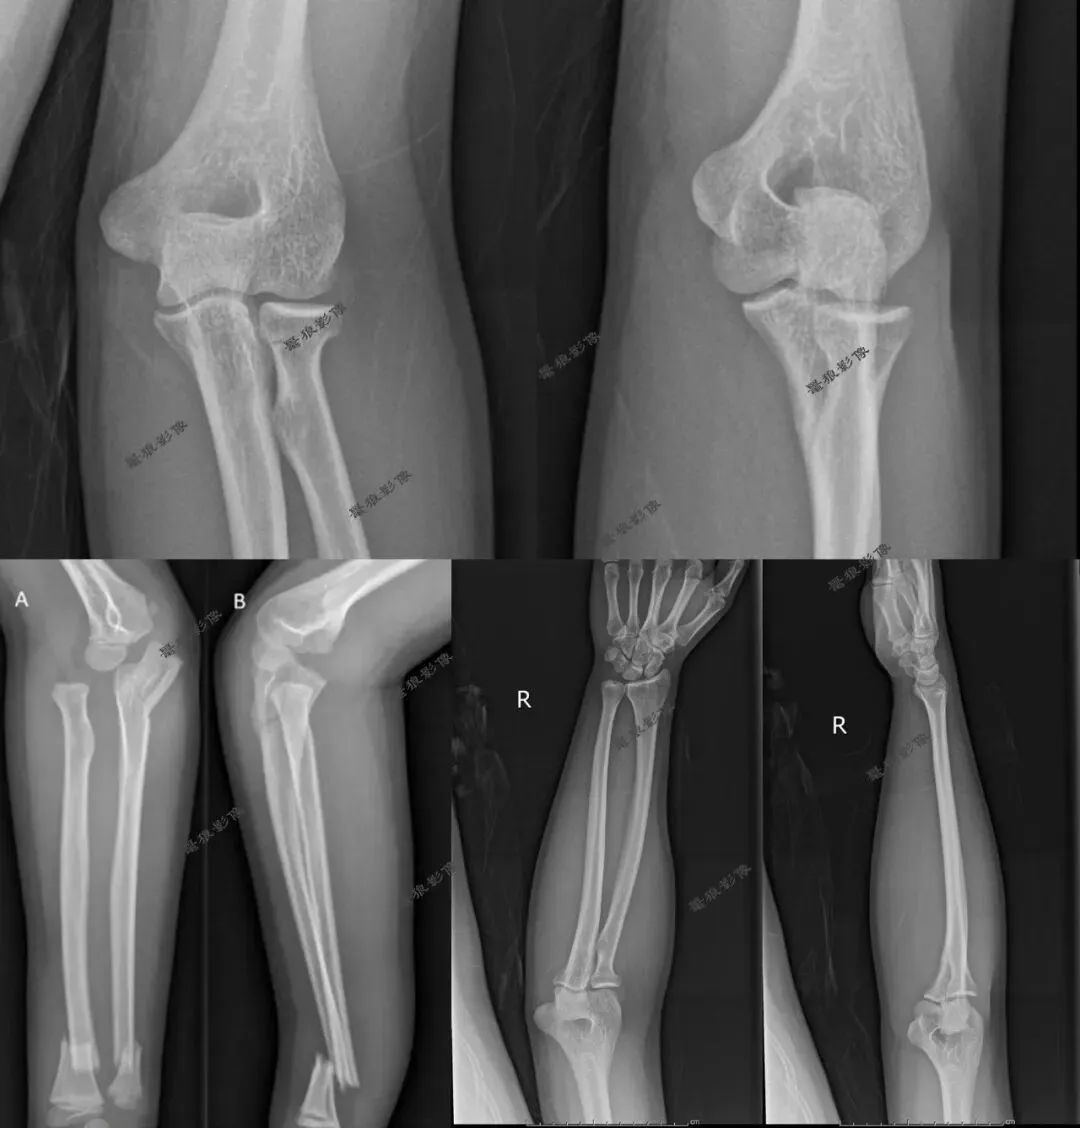

二、肘关节前后位

1.摄影要点:

(1)受检者面向摄影台就坐,前臂伸直,掌心向上,尺骨鹰嘴突置于探测器中心;

(2)照射野和探测器上缘包括肱骨下段,下缘包括桡尺骨上段;

(3)源-像距离为100cm;

(4)中心线对准肘关节(肘横纹中点)垂直射入探测器中心。

2.肘关节正位片标准影像显示:

(1)图像包括肱骨远端及桡尺骨近端,其关节间隙显示在图像正中;

(2)肘关节面呈切线位显示,明确锐利;

(3)鹰嘴窝位于肱骨内外髁正中稍偏尺侧;

(4)肘关节诸骨纹理和周围软组织清楚可见。

三、肘关节侧位

(1)受检者面向摄影台侧坐,曲肘成90°~120°,肘关节内侧贴近摄影台面;

(2)手掌面对受检者,拇指在上,尺侧朝下,成侧位姿势,肩部下移,尽量接近肘部高度;

(3)照射野和探测器上缘包括肱骨下段,下缘包括桡尺骨上段;

(4)源-像距离为100cm;

(5)中心线对准肘关节间隙,垂直射入探测器中心。

2.肘关节侧位片标准影像显示:

(1)肱骨远端与桡尺骨近端成90°~120°;

(2)尺骨与肱骨的关节间隙显示明确、锐利;

(3)肱骨内外髁重叠,呈圆形投影;

(4)肘关节诸骨纹理清晰,周围软组织层 次分明。

我们再看肘关节几组图片